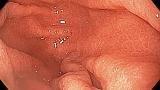

Клинические случаи: Нр ассоциированный гастрит

Диффузная гиперемия, расширенные желудочные поля, отсутствие собирательных венул.

Осмотр в режиме NBI и белом свете.

Эндоскоп: Olympus HQ190